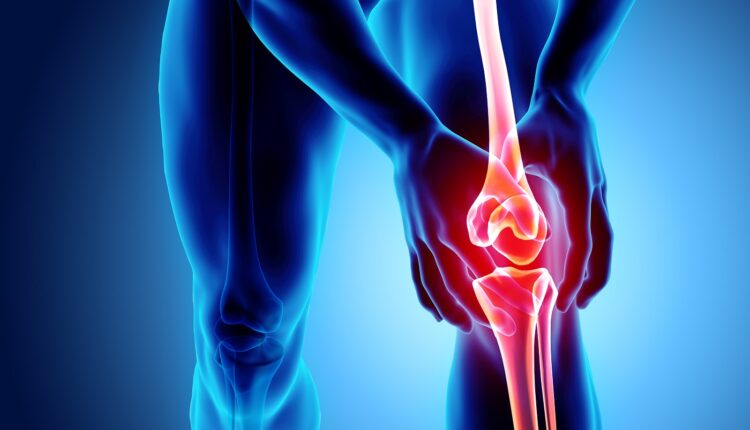

ابتكار علمي جديد قد ينهي آلام مرضى التهاب المفاصل

يعاني ملايين حول العالم من مرض التهاب المفاصل التنكسي. وفي خطوة قد تنهي آلام هؤلاء المرضى، فقد تمكن فريق من علماء جامعة كولومبيا الأمريكية، من زراعة ركبة بشرية حية في المختبر.

يعمل الابتكار الجديد على استعادة وظيفة المفصل الطبيعية وتخفيف الألم الذي يعيق الحركة اليومية. وصنع العلماء هيكلًا ثلاثي الأبعاد للركبة من مواد قابلة للتحلل الحيوي، ثم أضافوا إليه خلايا العظام والغضاريف، وعلى مدار نحو عام، تجدد الغضروف وأنسجة العظام، بينما تحلل الهيكل تدريجيًا، لتنتج ركبة كاملة جاهزة للزراعة.

وأوردت صحيفة “ديلي ميل” البريطانية في تقرير لها، أن العلماء يعملون حاليا على تطوير تقنية مستدامة، ليصبح هذا المفصل الجديد قابلًا للزرع في المرضى، ليُشكل حلًا دائمًا لهذه الحالة المؤلمة. واختبر العلماء النماذج الأولية في جثث لاختبار قدرتها على تحمل الوزن والمشي، ويخططون لزراعتها لدى حيوانات كبيرة قبل التجارب البشرية، ويمكن استخدام خلايا جذعية مأخوذة من المريض نفسه أو من متبرع، لضمان نجاح الزراعة، وعند زرع الركبة الحية، تتصل بالأوعية الدموية للجسم لتعمل تمامًا كالركبة الأصلية.

وتأتي هذه الإنجازات بدعم من وكالة مشروعات الأبحاث المتقدمة للصحة “ARPA-H” ضمن برنامج “NITRO”، الذي يهدف إلى تطوير علاجات تحفز المفاصل على الشفاء الذاتي، لتخفيف الألم أو القضاء عليه، وتقليل الحاجة لعمليات استبدال المفاصل الجراحية.